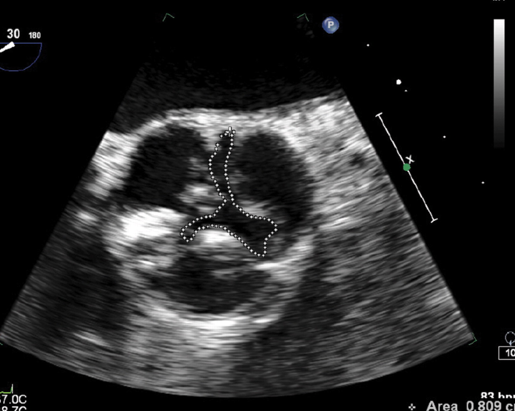

what is planimetry in ao stenosis?

tracing ao valve border to get an area

what planimetry measurement should raise concern for ao stenosis?

<2cm²

what does this represent?

planimetry of MV in diastole